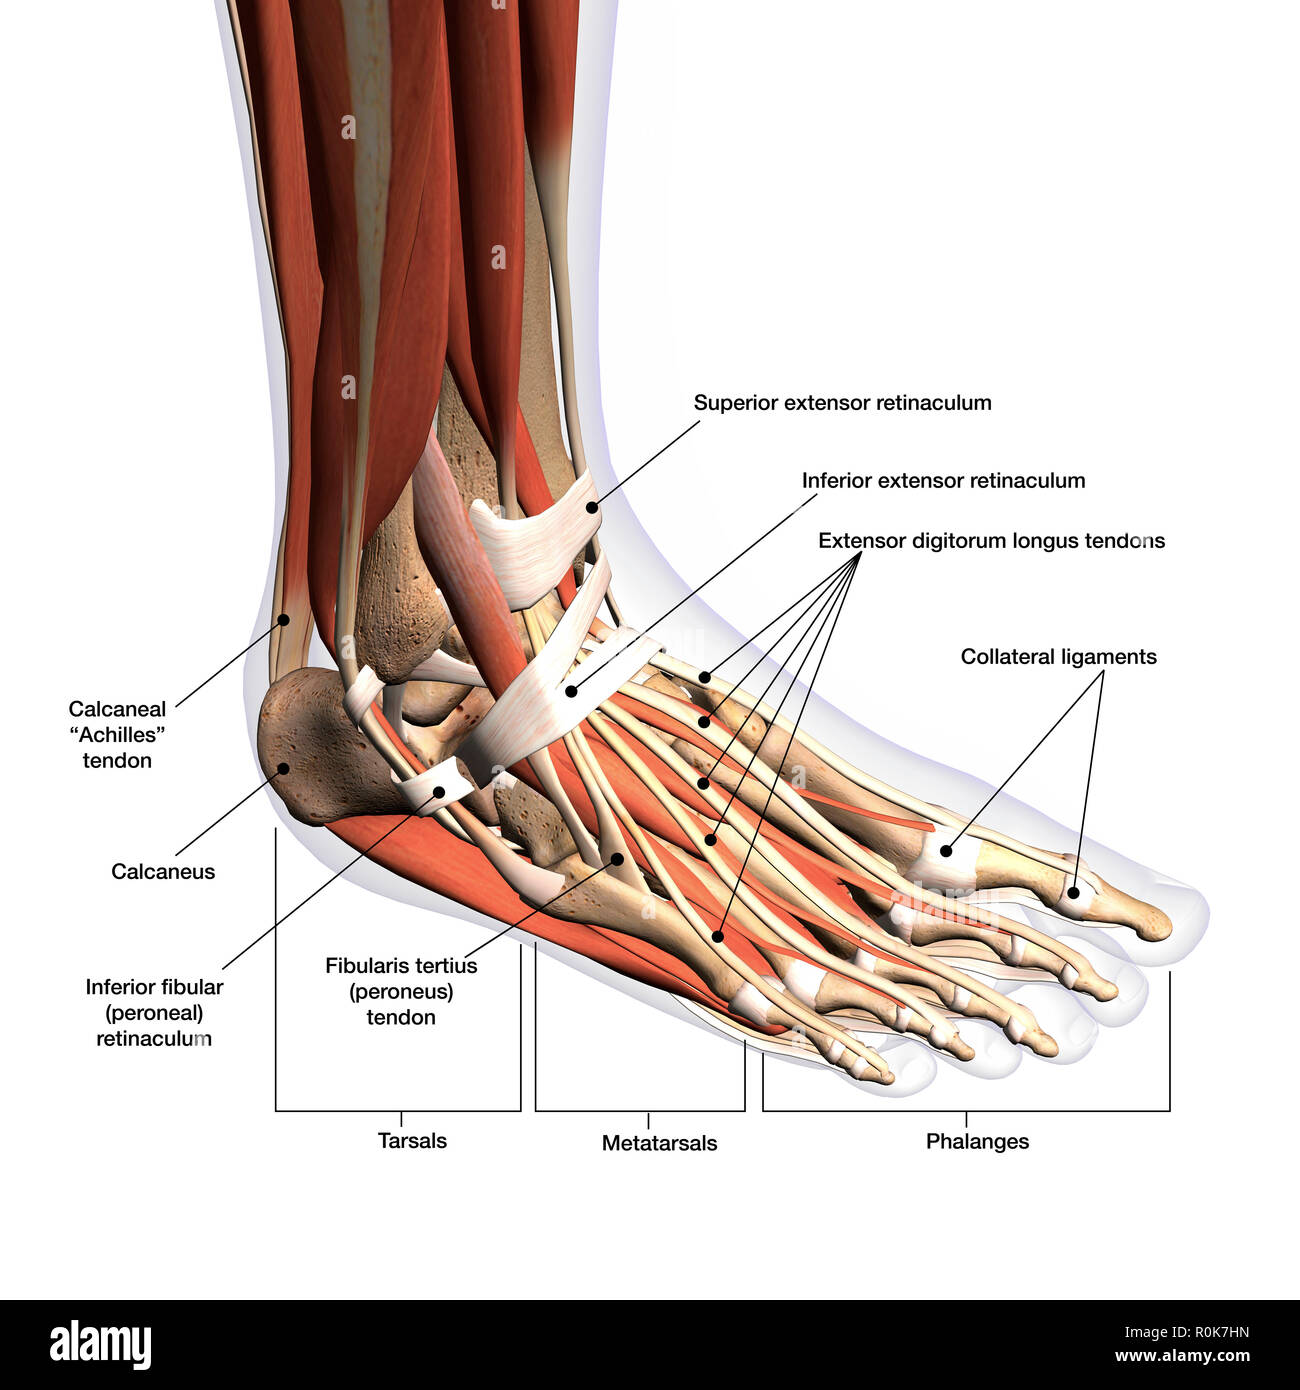

RFTCW7GT–L'articulation de la cheville, les tendons de la cheville anatomie pied eps vector illustration infographie 10